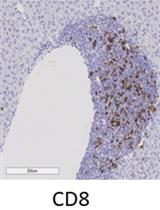

Count the WT1-positive cell numbers in a total field of smear under a light microscope (objective 20x or 40x).

Representative data: